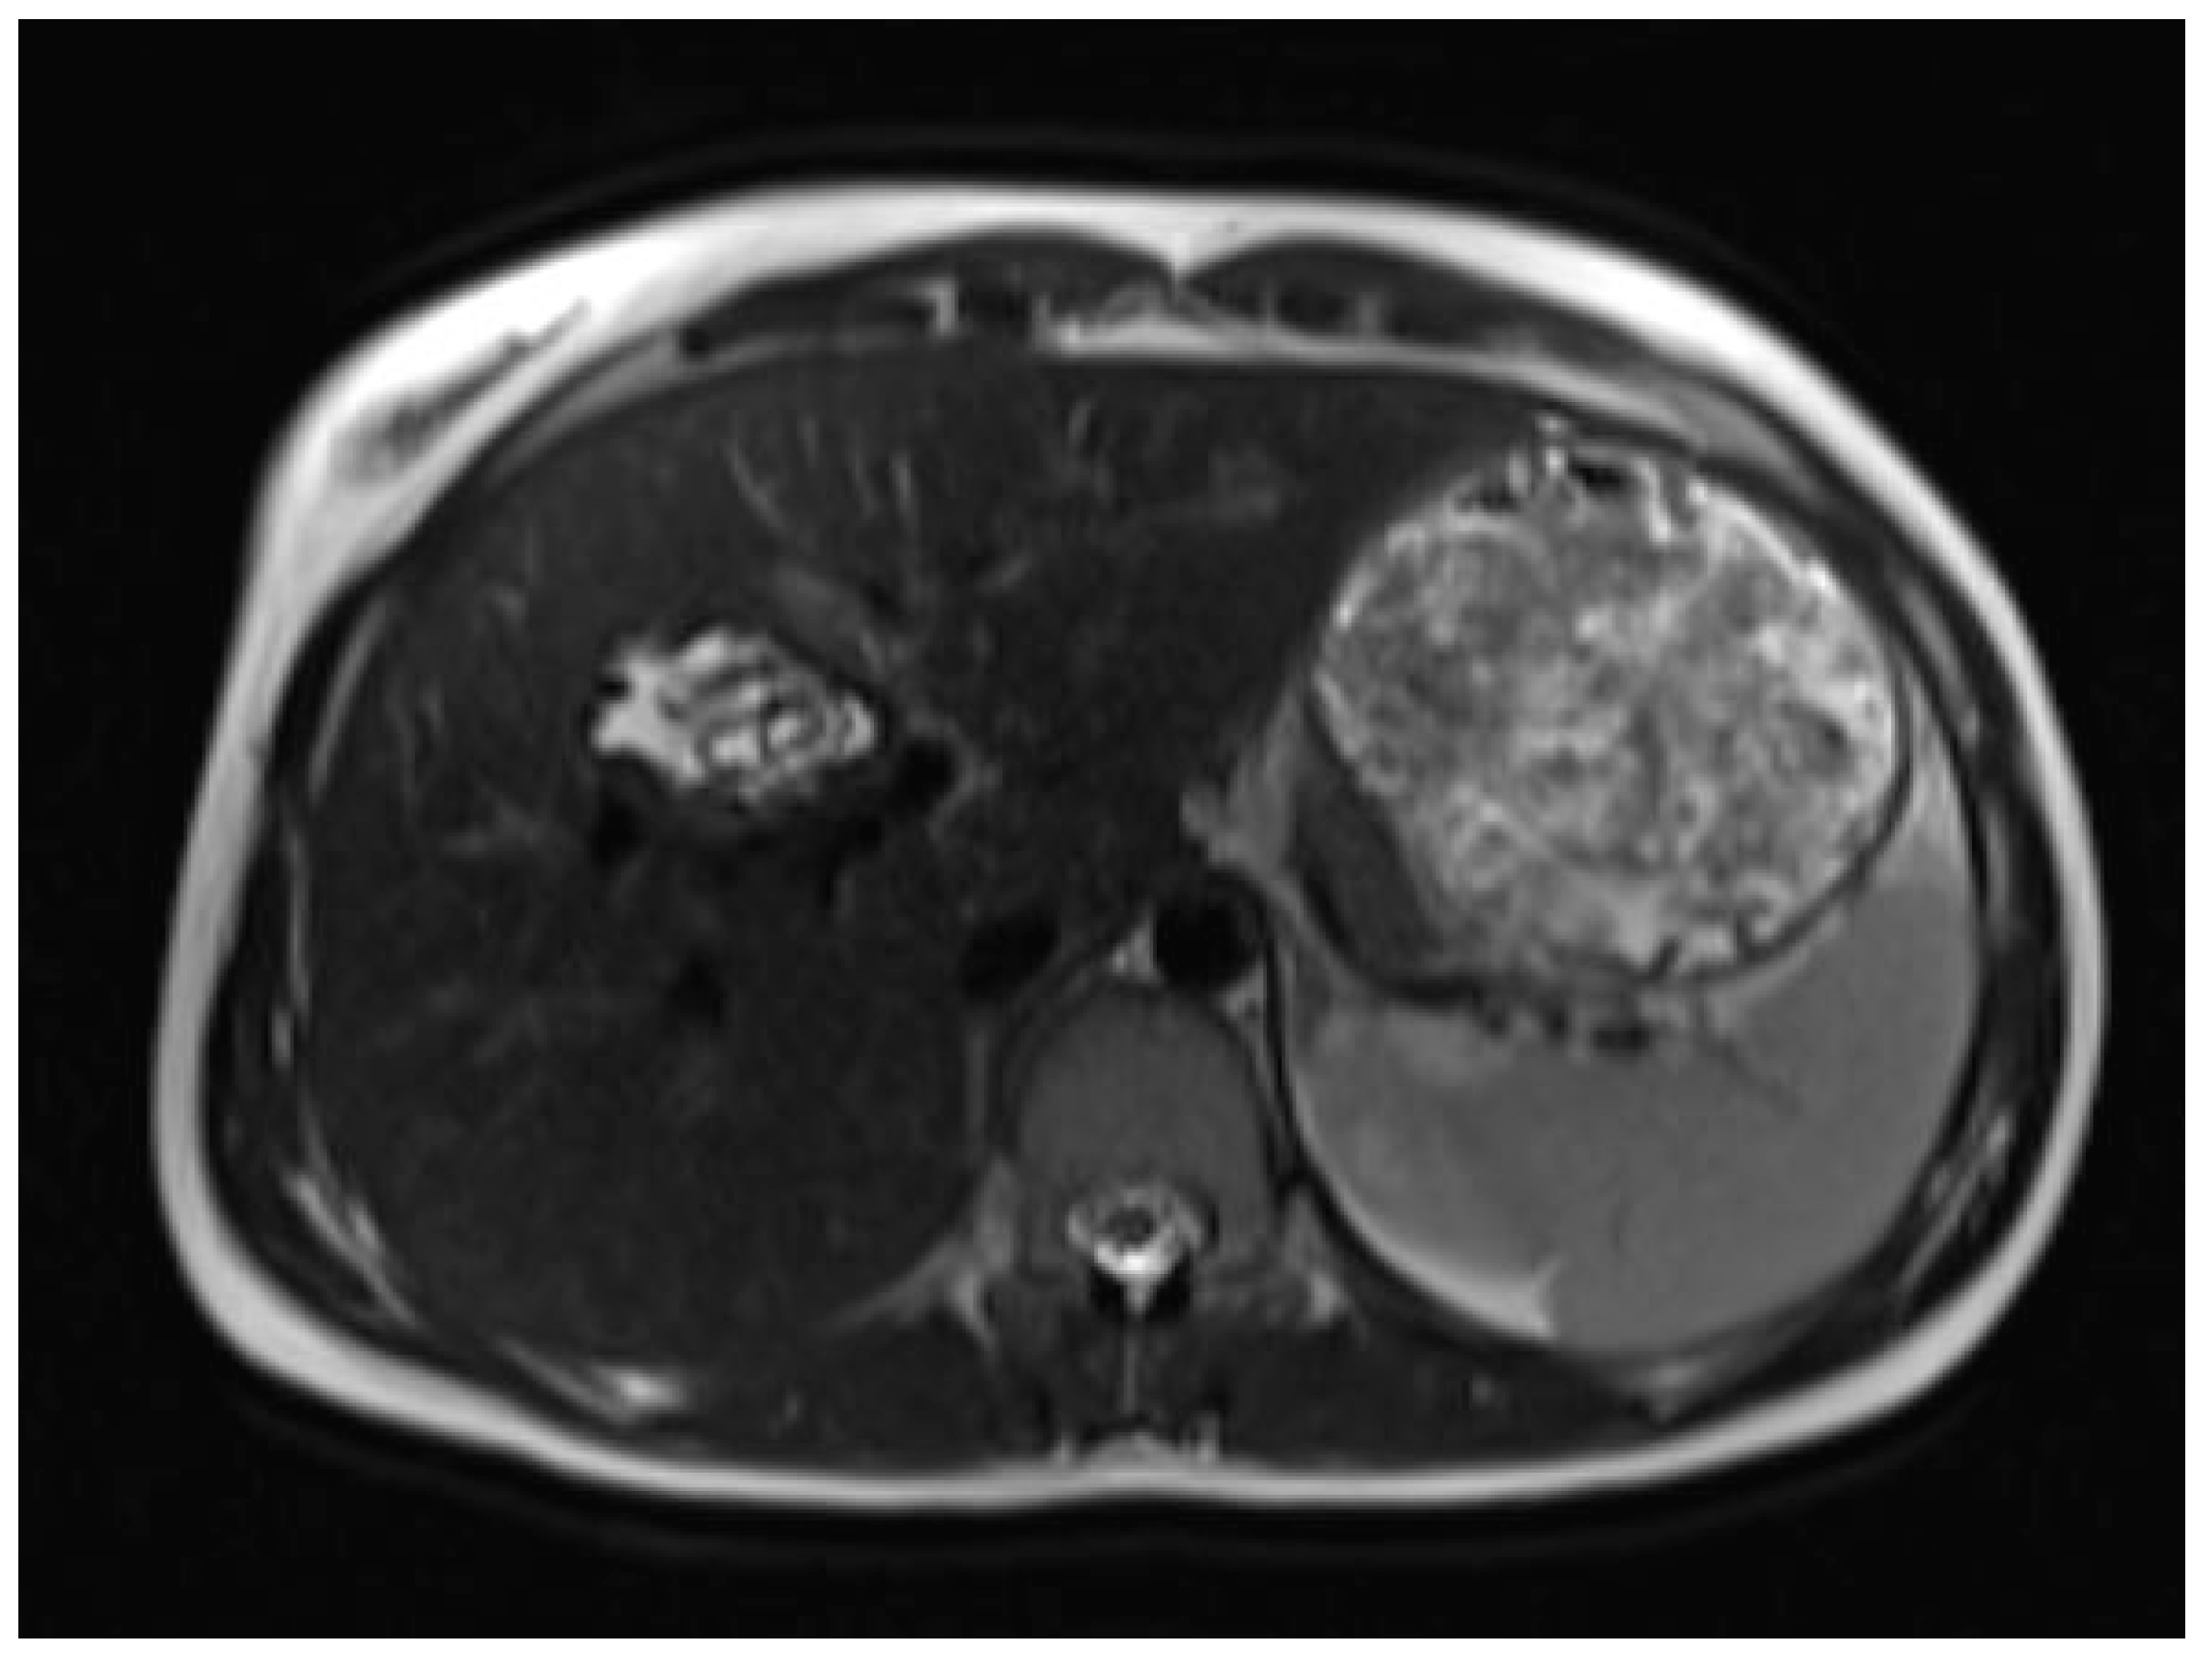

Six months later, a second ultrasound scan and a consecutive MRI scan to follow-up and control the success of the therapy were performed. The ultrasound revealed a decrease in the size of the cyst from 10 cm in maximal diameter to 9 cm and showed multiple circular septations, indicating an involuting cyst (Figure 7). In contrast to the preceding MRI scan, typical T2 hypointense membrane-like structures were observed within the lesion in T2WI. These represented most probably the floating membranes, the typical water-lily sign (Figure 8). T1WI (Figure 9) showed the cyst as a hypointense lesion, but the membranes could only be clearly observed in T2WI. Consecutively, the cyst was classified as WHO-CE3A.

Figure 8.

Second MRI scan: Axial T2W MRI scan, where floating membranes forming the water-lily sign after anthelmintic treatment, indicating stage WHO-C3a.

MR imaging clearly visualizes pericyst, matrix, and daughter cysts. The pericyst appears as a hypointense rim on both T1WI and T2WI due to its fibrous structure and the presence of calcifications. This is a specific feature of hydatid cysts, called the rim sign, mostly better visualized on T2WI [5]. The matrix represents hydatid-fluid-containing membranes of broken daughter vesicles, scolices, and hydatid sand [7]. The hydatid matrix appears hypointense on T1WI and significantly hyperintense on T2WI. However, the limitations of MRI scans are especially observed in stages CE4–CE5, as bigger calcifications are better observed on a CT scan. When daughter cysts are present, they are typically more hypointense than the matrix on T2WI, as observed in our case report [17] (Figure 1). If the membrane is separated, it can shift with movement, resembling a water lily floating on the surface of a pond, previously described as water-lily sign, which was seen in our case report as well [18] (Figure 8).